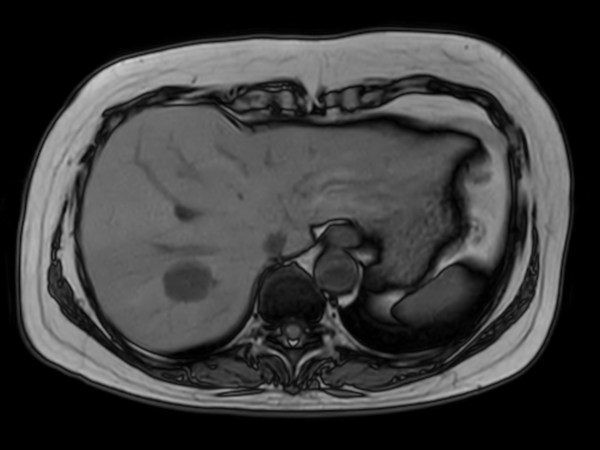

Liver hemangioma with Compressed SENSE

Axial T2w TSE